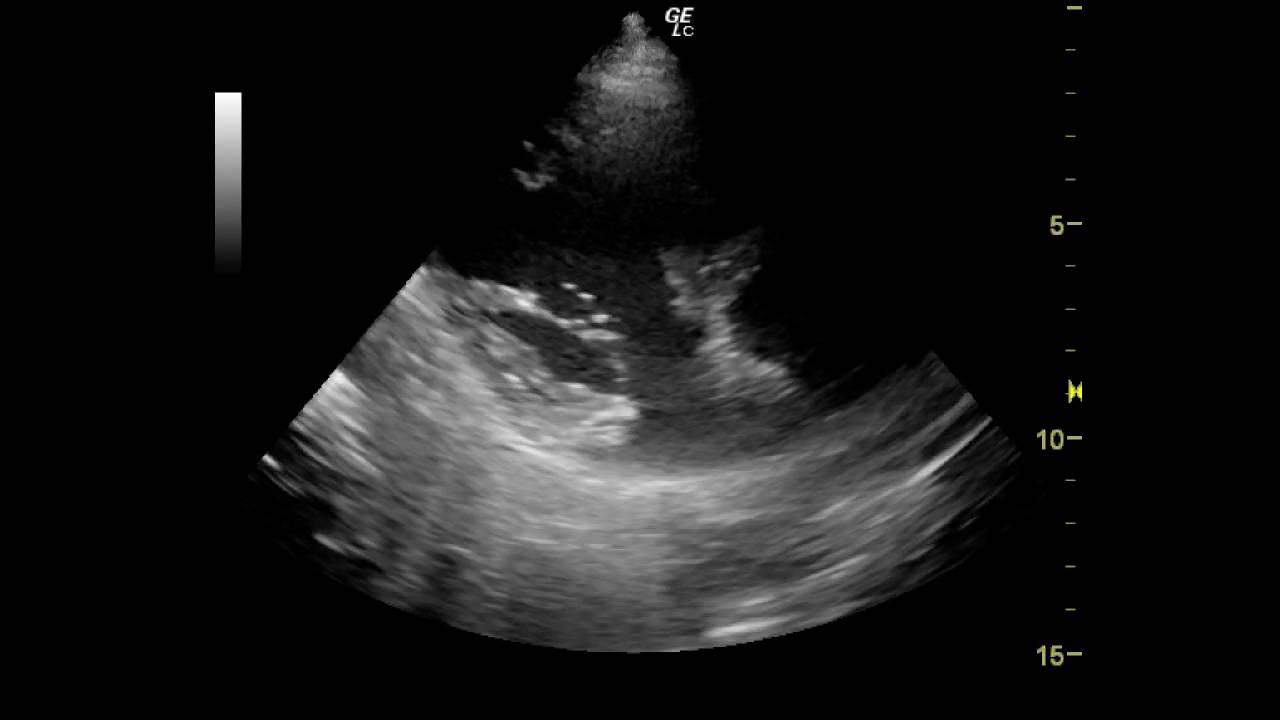

Дополнительная трабекула в полости левого желудочка представляет собой аномалию, которая может быть обнаружена при ультразвуковом исследовании сердца. Врачи отмечают, что такая структура часто является вариантом нормы и не всегда требует вмешательства. Однако важно учитывать, что наличие дополнительной трабекулы может быть связано с различными сердечно-сосудистыми заболеваниями. Специалисты подчеркивают, что в большинстве случаев она не представляет угрозы для жизни и здоровья пациента, особенно если не наблюдаются сопутствующие симптомы или функциональные нарушения. Тем не менее, для исключения возможных осложнений рекомендуется регулярное наблюдение и консультация кардиолога. Важно, чтобы пациенты не паниковали, а доверяли своему врачу, который сможет дать квалифицированную оценку состояния сердца.

Поскольку трабекула является врожденной аномалией, ее обычно обнаруживают во время стандартных диагностических обследований, проводимых в первый год жизни малыша. Все новорожденные проходят эхокардиоскопию, а при подозрении на дисплазию могут быть назначены электрокардиограмма (ЭКГ) и другие диагностические процедуры.

- Эхо-КГ (УЗИ) сердца. Это один из самых точных и информативных методов диагностики. Эхокардиография сочетает в себе УЗИ и ЭКГ, что делает ее более предпочтительной. Метод основан на отражении ультразвуковых волн от тканей организма.

Эхографическое исследование назначается пациентам, испытывающим одышку и перебои в работе сердца. У Эхо-КГ нет противопоказаний, однако ее проведение может быть затруднено у женщин с крупной грудью и у пациентов с деформированной грудной клеткой. Результаты обследования вместе с расшифровкой передаются пациенту, в которой указаны различные параметры, такие как размеры миокарда и желудочков, частота сердечных сокращений, объем выбрасываемой крови и ударный объем сердца. - ЭКГ. Электрокардиография используется для оценки работы сердца, однако она не может определить наличие перемычки. Эта процедура позволяет выявить только осложнения, вызванные данной аномалией. Часто назначается мониторинг сердечной активности – Холтер, который фиксирует работу сердца в течение суток.

Дополнительная трабекула в полости левого желудочка представляет собой аномалию, которая может быть обнаружена при ультразвуковом исследовании сердца (эхокардиографии). Это дополнительная мышечная структура, которая может варьироваться по размеру и количеству, и часто не вызывает никаких симптомов. Однако важно понимать, как она может влиять на сердечно-сосудистую систему и какие потенциальные риски она может нести.